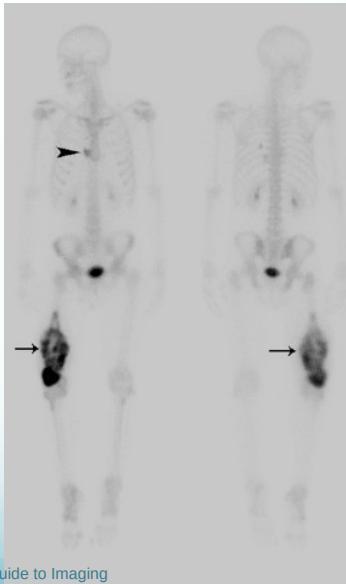

Additional Imaging

- Bone scan:

- Primary lesion

- Metastasis